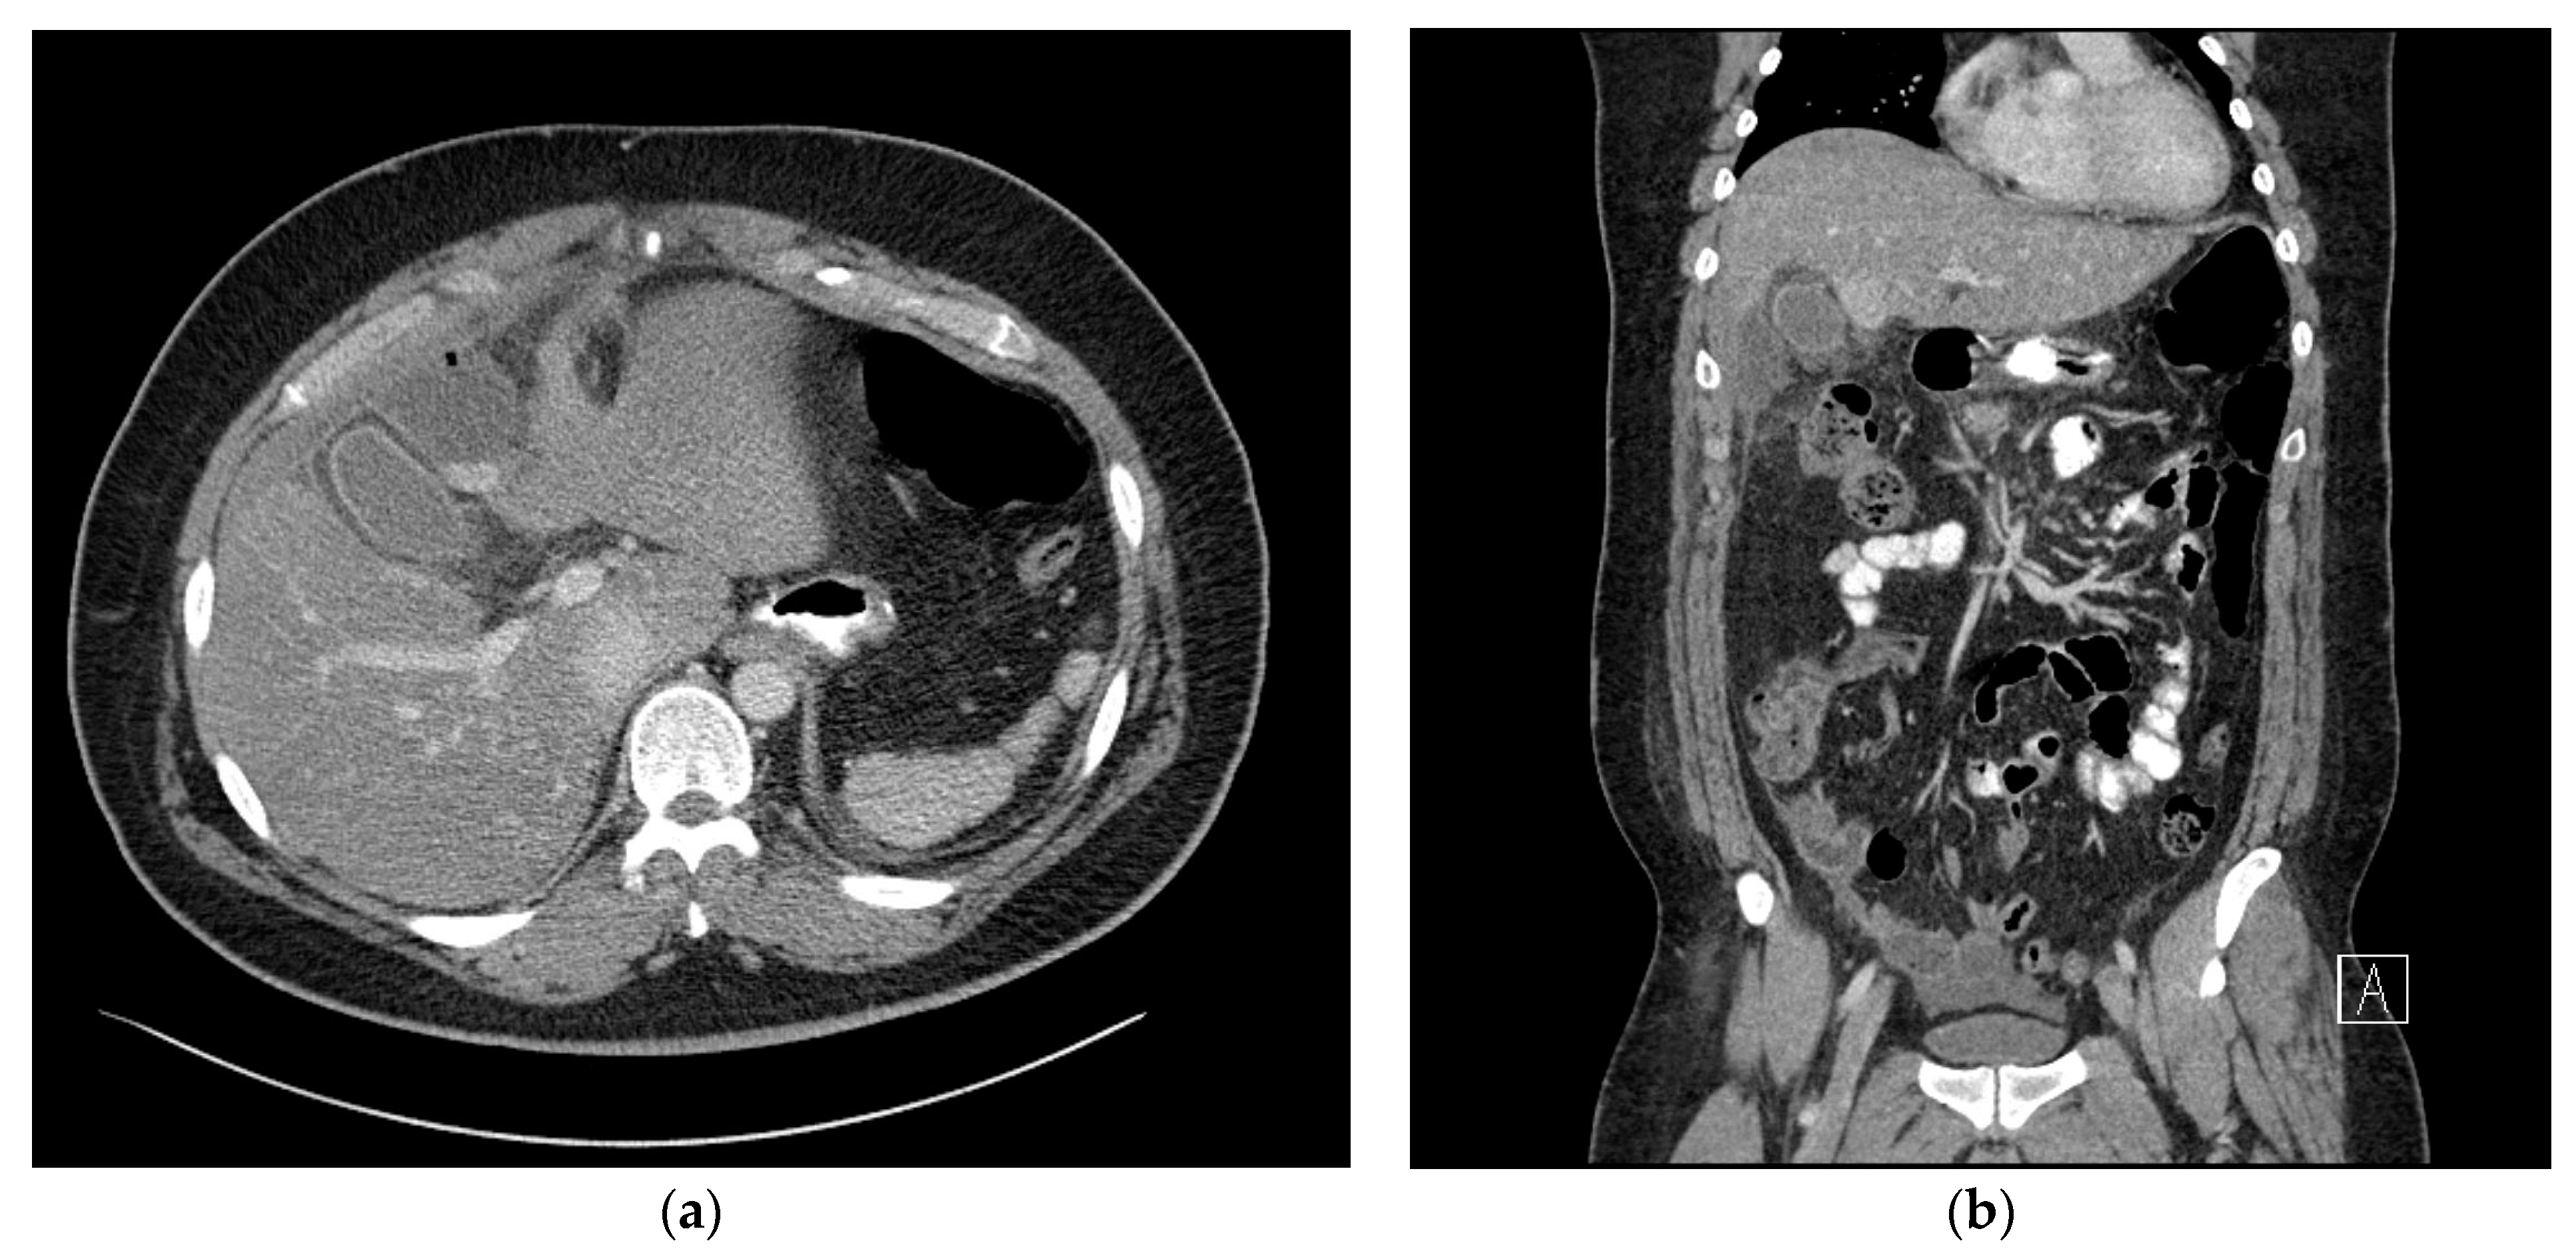

Subsequently, although the patient did not develop a fever, continued right upper abdominal mild tenderness was reported. On postoperative day 17, a follow-up abdominal CT scan was performed. which revealed a marked increase in multiple fluid collections in the right subhepatic space, measuring 135 × 105 mm, with the formation of an abscess wall, abut to the transverse colon. In addition, there was secondary inflammatory change in the colon (Figure 3a,b). At this time, the patient’s weight had reduced to 124 kg (%TWL: 9.2%, %EWL; 25.0%) and percutaneous drainage could be performed. In the pus culture, A. odontolyticus was identified. With a diagnosis of A. odontolyticus, and in consultation with the division of infectious disease, intravenous administration of 6.75 g of tazoperan per 8 h was initiated. A high dose of antibiotics was administered due to the patient’s obesity.

Figure 3. (a) Axial view of the abdominal computed tomography (CT) scan showing a marked increase in multiloculated fluid collections in the right subhepatic space. (b) Coronal view of the abdominal computed tomography (CT) scan showing multiloculated fluid collections in the right subhepatic space, abutting the transverse colon.